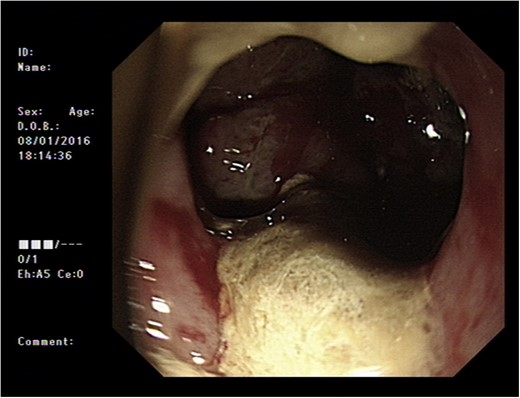

Initial upper GI endoscopy failed to enter the duodenum due to residue within the stomach with the appearance and odour of faeces noted. Abdominal computed tomography (CT) suggested a cavity with adherent ileum adjacent to the second part of the duodenum (Fig. 1). A contrast study was then undertaken demonstrating rapid flow of contrast into the terminal ileum and caecum originating from the duodenum (Fig. 2). Repeat upper GI endoscopy demonstrated an abnormal fungating fistulous communication between the duodenum and terminal ileum which permitted the full insertion of the endoscope (Figs 3 and 4). Biopsies were consistent with diffuse B-cell lymphoma (DLBCL) in accordance with the WHO classification.